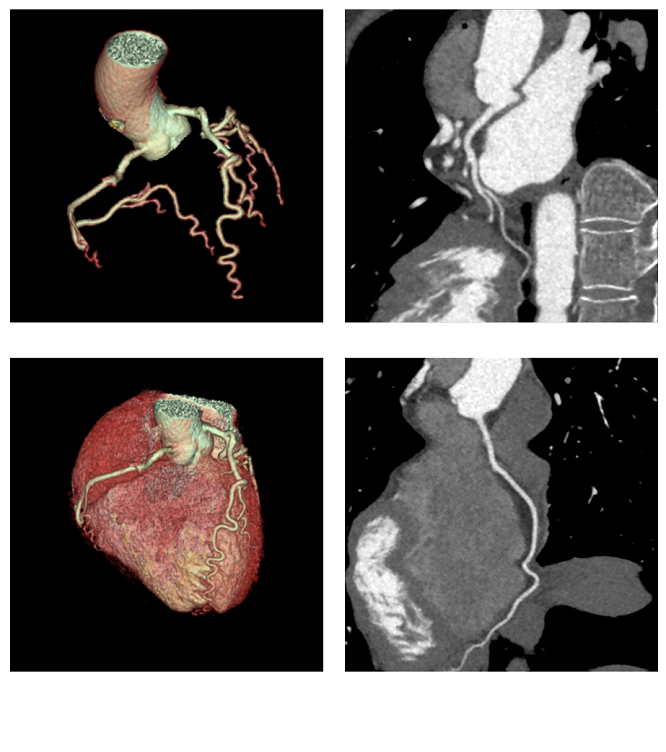

结论 160mm宽体探测器与ASiR-V的迭代重建技术,能够确保使用超低的扫描剂量和极低的碘对比剂用量,来排除冠心病。(图2) Thanks to the 160mm coverage and ASIR-V the exam was performed with ultra-low dose and very low iodine load to exclude CAD.

图2: CCTA 图像